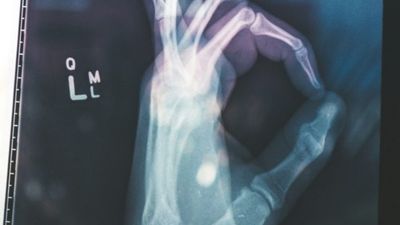

Siç pretendohet, modeli kryesor MedGemma 27B nuk lexon vetëm tekstet mjekësore siç bënin versionet e mëparshme; ai në fakt mund të "shikojë" imazhet mjekësore dhe të kuptojë se çfarë po sheh aty, përcjell Telegrafi.

Qofshin rreze X të kraharorit, diapozitiva patologjike apo të dhëna të pacientëve që potencialisht përfshijnë muaj ose vite, ai mund t'i përpunojë të gjitha këto informacione së bashku, ashtu siç do të bënte një mjek.

Veç kësaj, Google ka lansuar edhe MedSigLIP. Me vetëm 400 milionë parametra, ai është trajnuar për të kuptuar imazhet mjekësore në mënyrë të thellë.